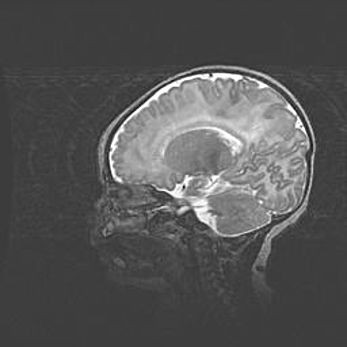

Открытая гидроцефалия.

Возраст: 6 месяцев 15 дней

Вес: 6200 г

Пол: женский

Окружность головы: 41 см

Срок гестации: 38 недель

Гидроцефалия головного мозга у новорожденных – это скопление избыточного количества цереброспинальной жидкости в головном мозге. Ее избыточное скопление в мозге приводит к патологическому расширению желудочков мозга (четырех полостей, расположенных в глубине белого вещества мозга, заполненных цереброспинальной жидкостью и связанных узкими проходами).

Открытый тип гидроцефалии (сообщающаяся) наблюдается тогда, когда нарушен механизм всасывания ликвора в системный кровоток. При этом типе причиной заболевания чаще всего является перенесенные ранее инфекции (например: менингит),  либо же наличие крови в субарахноидальном пространстве.